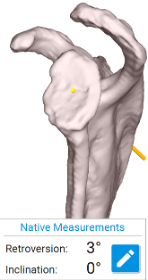

BH is a right hand dominant 70-year-old female, who is retired and moderately active. She presents with 8 months of progressively worsening left shoulder pain affecting her ADLS, sleep and recreational activities. She is 10 years s/p a right anatomic total shoulder arthroplasty. Radiographs and advanced imaging reveal glenohumeral joint advanced degenerative joint disease with an intact rotator cuff. Preoperative planning reveals a native 3 degrees of retroversion with 0 degrees of inclination. As she was extremely happy with the fully functional contralateral shoulder she has enjoyed for the past decade, she was interested in the same solution – an anatomic total shoulder arthroplasty.

At age 70 secondary rotator cuff tears following anatomic total shoulder arthroplasty must be weighed against complications and postoperative function of reverse shoulder arthroplasty [3]. Advita Predict+ was able to demonstrate comparable postoperative function, scores, pain, and complications. A decision was reached to proceed successfully with an anatomic total shoulder arthroplasty.